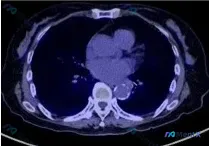

整理了一份骨病灶的随访影像资料,有几个点感觉挺有意思,放出来讨论下: 现有核心影像表现: 1. CT骨窗:右T9及右侧第9肋骨病灶,可见进一步影像学改善 2. PET-CT(结合提供的分析):病灶部位无明显FDG异常高摄取,与背景本底基本一致 3. 额外发现:降主动脉管壁可见明显弧形钙化斑块,提示动...